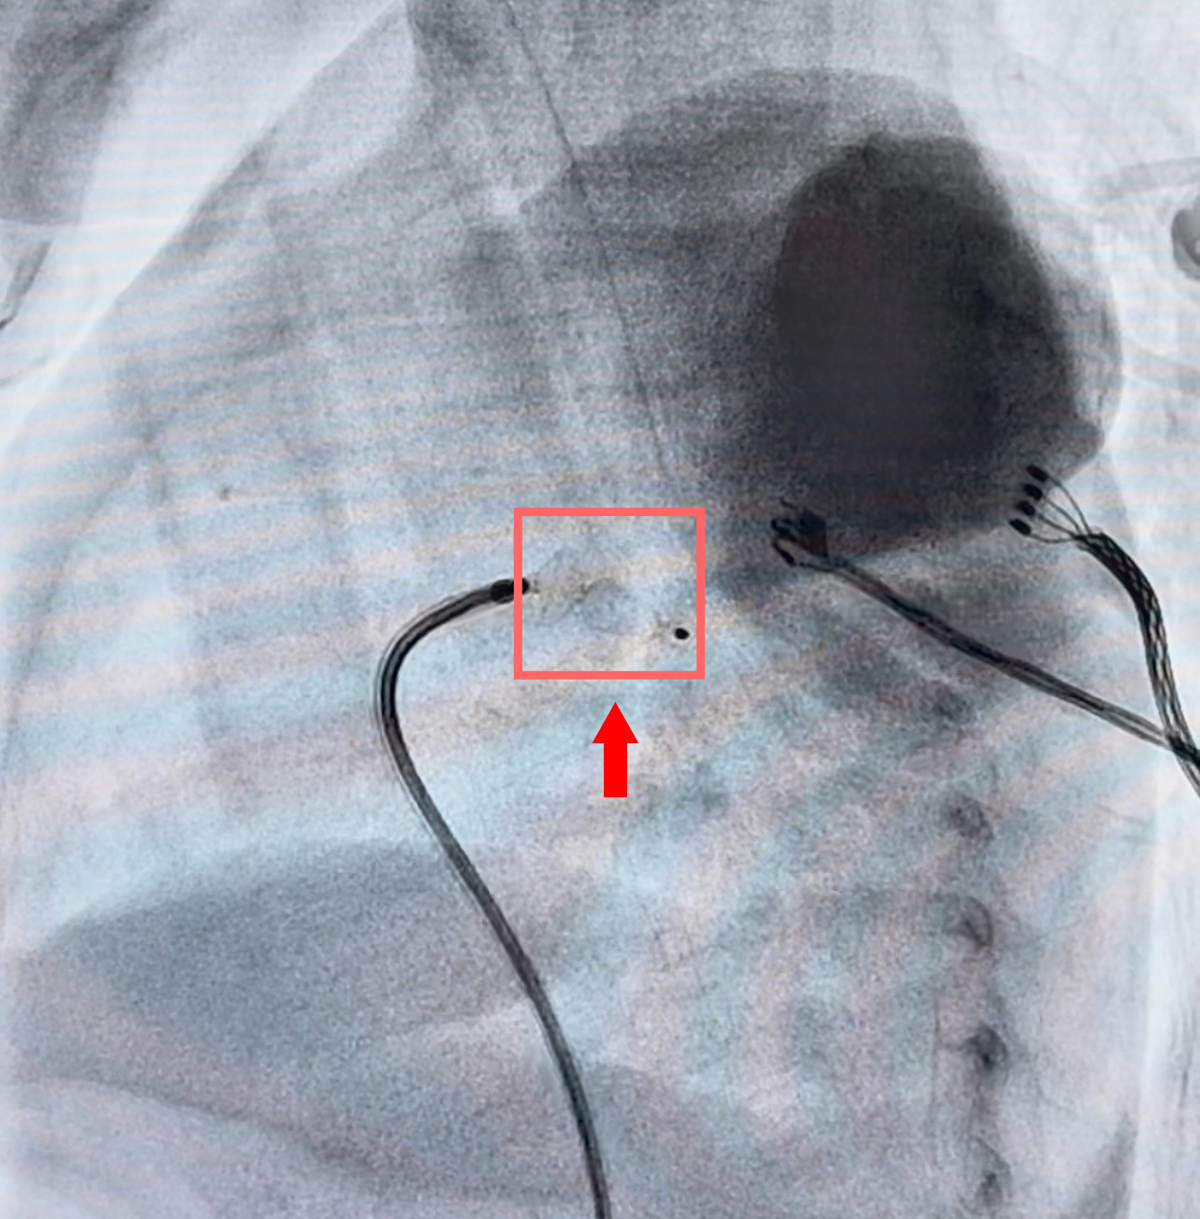

4月8日上昼,在全身麻醉及全程超声率领下,介入团队通过穿刺股静脉建造通说念。在X光与超声的双重“导航”下,李恒主听凭借深通技能,谨防翼翼地将导丝和运送鞘穿过比头发丝粗不了几许的血管,精确定位到未闭合的动脉导管处。跟着封堵器的完整开释,造影深远:动脉导管分流短暂灭绝!

整台手术操作时分仅约40分钟,出血量一丝。术后即刻超声深远:封堵器位置踏实,无残余分流,腹黑噪音灭绝。“手术奏效了!”术后,橙橙的心功能明显改善,呼吸机参数奏凯下调,人命体征牢固。